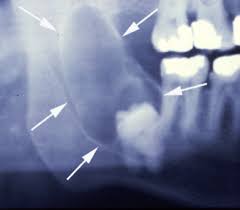

ฟันคุดคือ ฟันที่ไม่สามารถขึ้นได้เต็มที่ตามปกติ โดยมากมักจะเป็นในฟันกรามซี่สุดท้าย ( ในรูปคือ ฟันสีส้ม) สามารถเป็นได้ทั้งฟันบน และ ล่าง แต่ส่วนมากฟันล่างจะพบว่าเป็นฟันคุดได้มากกว่า ส่วนฟันซี่อื่น ๆ ถ้าขึ้นมาได้ไม่เต็มซี่ก็อาจเรียกว่าฟันคุดได้เหมือนกัน แต่ไม่ค่อยพบครับ

ทีนี้ฟันคุดมากคุดน้อยขึ้นอยู่กับตำแหน่งของฟัน ว่าฝังลึกลงไปในกระดูกมากน้อยแค่ไหนและมีความเอียงมากแค่ไหน (ลองดูรูปประกอบครับ)

ถ้ายิ่งฝังลึกลงไปมาก หรือมีความเอียงมากก็จะยิ่งทำยาก